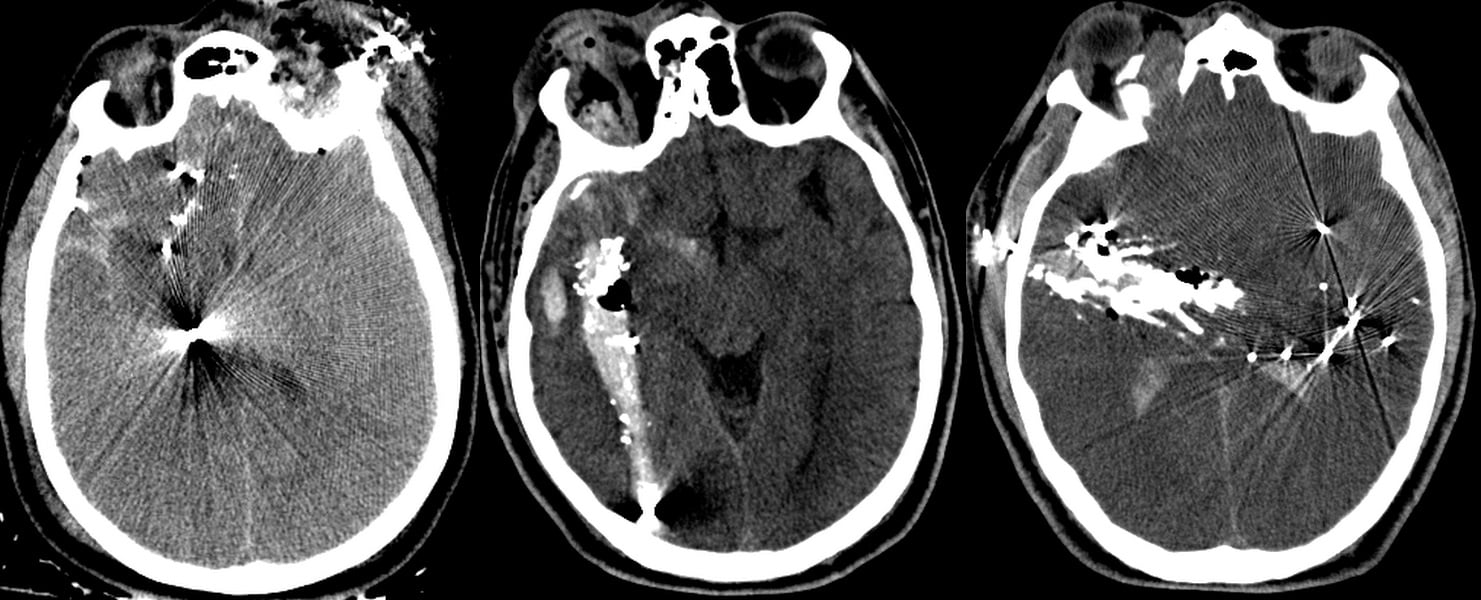

Outcome Prediction in Penetrating Brain Injury

In collaboration with several other trauma

centers (University of Maryland Shock Trauma, Yale, Baylor College of Medicine and Vanderbilt Medical Center), our group has created the SPIN-score (Muehlschlegel S, Ayturk D, Ahlawat A, et al.) to predict survival after penetrating brain injury. We are currently working hard to validate this parsimonious logistic regression prediction score. (This has been featured in Neurology Today).